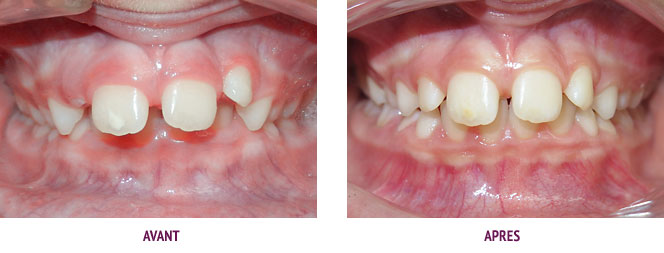

Cas 23 : Stimulation précoce de la croissance de la mâchoire inférieure

Le déficit de croissance de la mâchoire inférieure est tel que le menton est très reculé et la lèvre inférieure vient se positionner derrière les incisives supérieures. Dans ce contexte, la croissance est bloquée par l’interposition labiale et le verrouillage de l’occlusion (arcade supérieure étroite, incisives inférieures en appui sur la gencive du palais derrière les incisives supérieures). En l’absence de traitement précoce, nous orientons la patiente vers un traitement ortho-chirurgical.

Un activateur stimulant la croissance de la mâchoire inférieure a été très bien porté pendant 1 an. Le profil a énormément évolué avec une avancée impressionnante du menton. De bons rapports occlusaux d’avant en arrière ont été obtenus. Le but de cette phase interceptive était de réduire le décalage squelettique et non d’aligner ou de corriger l’excès de recouvrement antérieur. Ceci a été traité à l’adolescence avec un appareil orthodontique classique en 1 an.